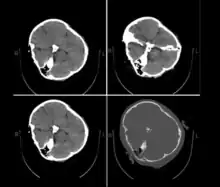

On 16 September 2022, the 22-year-old Iranian woman Mahsa Amini,[lower-alpha 1] also known as Jina Amini,[lower-alpha 2][1][2][3] died in a hospital in Tehran, Iran, under suspicious circumstances. The Guidance Patrol, the religious morality police of Iran's government, arrested Amini for allegedly not wearing the hijab in accordance with government standards. The Law Enforcement Command of the Islamic Republic of Iran stated that she had a heart attack at a police station, collapsed, and fell into a coma before being transferred to a hospital.[4][5] However, eyewitnesses, including women who were detained with Amini, reported that she was severely beaten and that she died as a result of police brutality,[6][7][8] which was denied by the Iranian authorities.[9] The assertions of police brutality, in addition to leaked medical scans,[10] led some observers to believe Amini had a cerebral hemorrhage or stroke due to head injuries received after her arrest.[11]

Published hospital pictures show Mahsa Amini bleeding from the ear and with bruises under her eyes. In an 18 September letter, Doctor Hossein Karampour (the top medical official in Hormozgan province), pointed out that such symptoms "do not match the reasons given by some authorities who declared the cause to be a heart attack... (they are instead consistent with) a head injury and the resulting bleeding."[63] This was also confirmed by alleged medical scans of her skull, leaked by hacktivists, showing bone fracture, hemorrhage, and brain edema.[10][64]

By 21 September, the hospital had released preliminary CT scans. Government supporters stated the CT scans showed psychological stress caused by a previous brain operation; critics stated the scans showed physical beating and trauma. The Iranian government stated Amini had a brain operation at the age of five.[66]